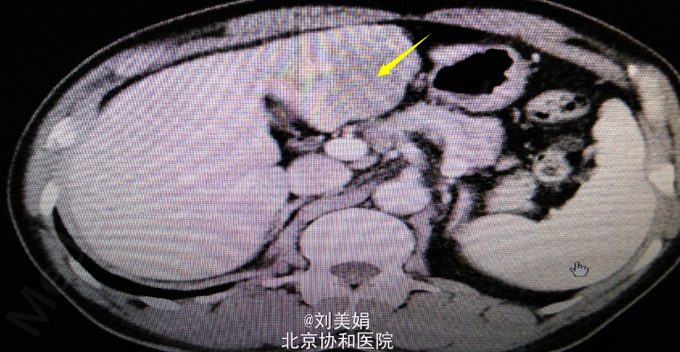

患者 男 58岁 主 诉:乙肝20余年,发现肝脏占位1月余 现病史:患者乙肝病史20余年,间断口服保肝药物,并定期复查肝功,肝功能目前可。每年常规行腹部B超检查,均未见明显异常。1月前体检,行腹部CT发现肝脏占位。患者无畏寒发热、腹痛腹胀、恶心呕吐、皮肤黄染等。于2015年7月10日我院门诊就诊,行腹部增强CT+三维重建示:肝左叶见不规则状稍低密度影,最大截面约为6.0cm×4.6cm,增强后动脉期可见明显强化,门脉期及延迟期强化程度减低,呈“快进快出”强化,肝左动脉分支参与病变供血,门静脉左支局部明显变细,肝门区、小网膜囊内、腹膜后多发淋巴结,部分增大。考虑:肝左内叶占位,考虑恶性病变可能性大;肝左动脉分支参与病变供血,门静脉左支局部明显变细,局部受累可能;肝门区、小网膜囊内、腹膜后多发淋巴结,部分增大。肝肾功:AST 67U/L,LD 254U/L,TBil 13.2μmol/L,DBil 4.5μmol/L,Cr(E) 79μmol/L,ALT 45U/L,Alb 48g/L,GGT 47U/L。

腹部增强CT+三维重建:肝左内叶占位,考虑恶性病变可能性大;肝左动脉分支参与病变供血,门静脉左支局部明显变细,局部受累可能;肝门区、小网膜囊内、腹膜后多发淋巴结,部分增大;双肾多发结石;左肾小囊肿;腹主动脉及其分支动脉粥样硬化性改变;胸腰椎骨质增生。